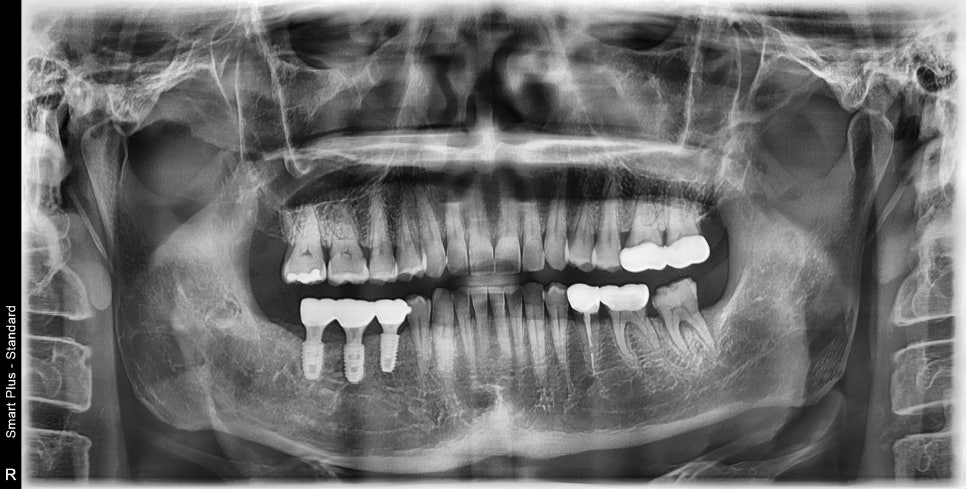

약 4개월후 빨간선으로 표시된것 처럼 주변 뼈들이 회복이 된것을 확인 후 임플란트 수술이 진행되었습니다.

이렇게 벽을 이루고 있는 뼈들이 녹아있는경우는 치조골 이식후 회복기간을 기다렸다 하는경우가 예측이 좀더 좋습니다

이렇게 발치가 필요한 경우

임플란트 수술은 필요하지만

수술 시기를 결정하는방법은

해당부분의 컨디션에 따라 얼마든지 달라질수 있기에

3D CT를 동반한 진단을 같이 받아보시는 것을

권해드립니다